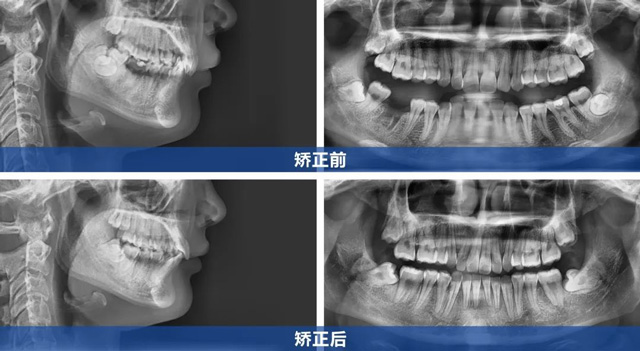

顧客上前牙內(nèi)扣且咬合較深,屬于內(nèi)傾性深覆合(即上牙覆蓋下牙的范圍較大,且上前牙向內(nèi)傾斜,幾乎完全覆蓋住下牙)。矯正內(nèi)傾牙時需精準(zhǔn)控制前牙外移角度,既要解除深覆合,又要避免上唇過度前凸影響面型。

同時,顧客就診前缺右下第一磨牙,左下第一磨牙嚴(yán)重齲壞需要拔除,下頜兩個磨牙空缺跨度較大,關(guān)閉間隙過程中需控制下后牙移動的角度,避免出現(xiàn)鄰牙傾斜。

【治療方案】

在與顧客充分溝通后,根據(jù)顧客訴求及CBCT檢查結(jié)果,我們制定了拔牙矯治的方案:

1、上頜對稱性拔除兩顆第一前磨牙,為前牙調(diào)整創(chuàng)造空間

2、拔除左下齲壞嚴(yán)重的第一磨牙

3、采用金屬托槽精細(xì)調(diào)整牙齒移動軌跡,排齊牙齒,解除內(nèi)傾性深覆合

4、利用下后牙向前移動來關(guān)閉間隙

5、收完間隙后再整體進(jìn)行精細(xì)調(diào)整

楊女士成功告別牙套后,曾經(jīng)內(nèi)扣的上前牙變得平直,面部輪廓更顯自然流暢,如今的她,笑容自信綻放,舉手投足間盡顯開朗。